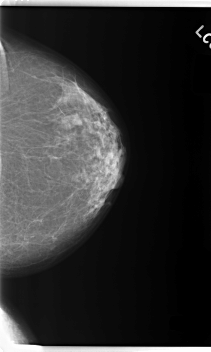

C_0275_1.LEFT_MLO

LEFT_MLO LINES 5904 PIXELS_PER_LINE 3616 BITS_PER_PIXEL 12 RESOLUTION 50 NON_OVERLAY